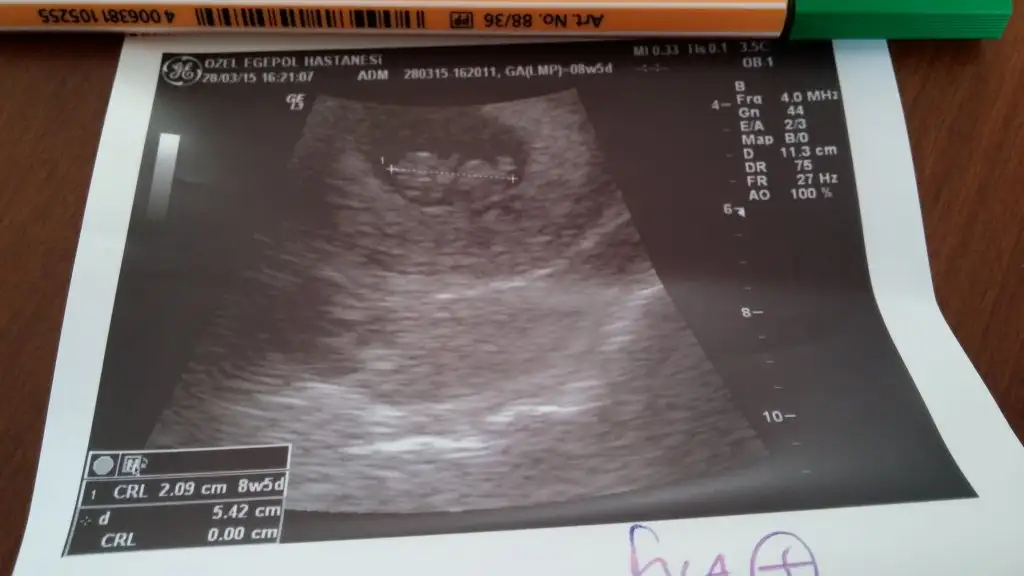

Ben de tahmin alabilir miyim?

12 haftaligim :KK36::KK46::nazar: